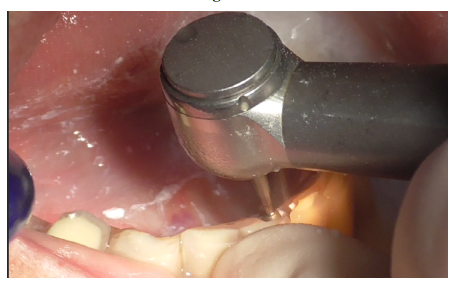

Removal of the prosthetic structure began by eliminating cement covering the prostethic abutment (Figures 3-5), followed by unscrewing the abutment (Figure 6) to facilitate the removal of the prosthesis.

Figure 4

Figure 5